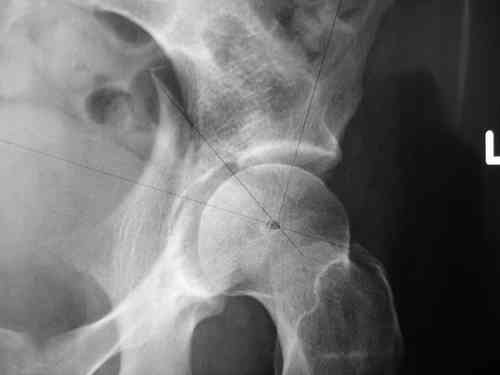

Маленькая иллюстрация (около 5 лет после травмы). Результат плохой - укорочение, хромота, периодически боли в спине, но больной отказывается от операции, видимо, не так все трагично.